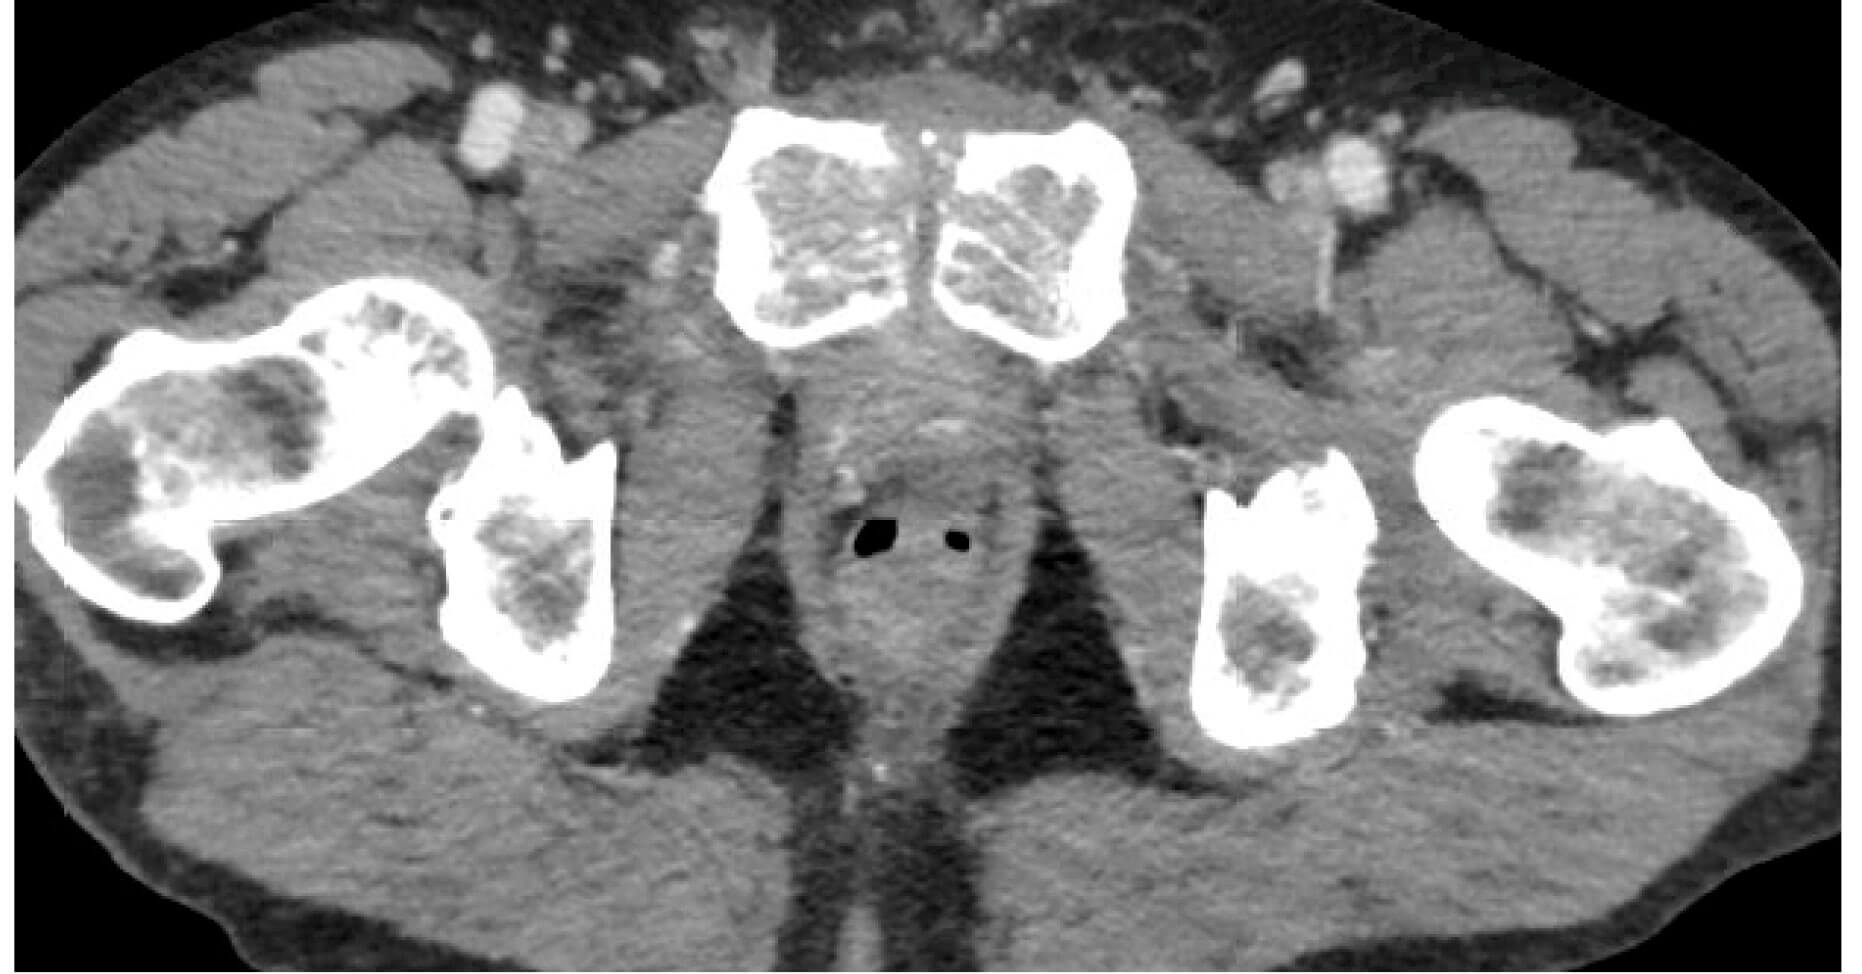

Days after a treatment course was completed for the above UTI, the patient’s groin symptoms became intolerable, and he was admitted to hospital for management. A CT scan was performed to rule out a pelvic collection, and a flexible cystoscopy was performed followed by bladder catheterisation. The cystogram showed no leak, but the CT scan suggested osteomyelitis (Figure 2a). An MRI pelvis (Figure 2b) was requested in order to confirm or refute the presumptive diagnosis made on CT. The MRI report concluded that changes seen in the bone were that of infective osteitis pubis and osteomyelitis. There was also an associated small amount of enhancing fluid at pubic symphysis posteriorly along with mild oedema of right obturator muscles.

Figure 2a: Post RARP CT image showing loss of articular surfaces of pubic symphysis. No collection.